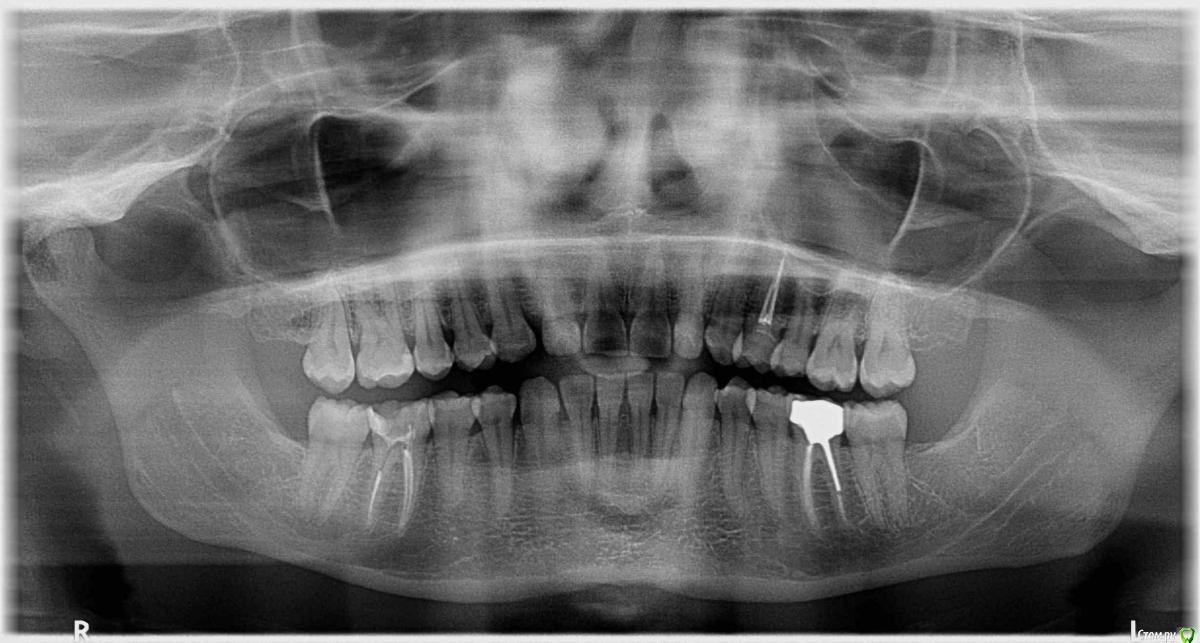

malinas Опубликовано 3 февраля, 2019 Поделиться Опубликовано 3 февраля, 2019 (изменено) Добрый вечер. После лечения пульпита 36 и 46 зуба через некоторое время начали болеть (на постукивание - тоже боль). Снимок прилагаю. Левый зуб после лечения покрыт металлокерамической коронкой на культевой вкладке (кобальт-хром), правый под временной пломбой, также предполагалось покрывать его коронкой, по аналогии с левым. Что это может быть? Периодонтит? И как перелечиваются такие зубы? Нужен ли микроскоп? Изменено 3 февраля, 2019 пользователем malinas Ссылка на комментарий

malinas Опубликовано 3 февраля, 2019 Автор Поделиться Опубликовано 3 февраля, 2019 36 все 4 месяца был чувствительным, сам по себе не болел, но трогать его было ощутимо. Ортопед делал снимок, ничего не увидел и продолжил своё лечение, сказав, что это могут быть постпломбировочные боли (хотя через месяц мне показалось странным наличие болей). И две недели назад, после ОРВИ, я уже поняла, что болит конкретно этот зуб, причем сильно, по нему больно было стучать, боль при накусывании, снова сделали снимок (уже стояла постоянная коронка), сказали всё идеально. А вот 46 зуб дал о себе знать где-то через 3 недели после лечения, больно на него нажимать сбоку и сверху и побаливает сам по себе (в общем, такие же ощущения, как с 36). Ссылка на комментарий

DmitrySH Опубликовано 5 февраля, 2019 Поделиться Опубликовано 5 февраля, 2019 На снимках действительно все хорошо выглядит.Но раз беспокоит, то лучше с 46 начать и сделать ревизию каналов Ссылка на комментарий